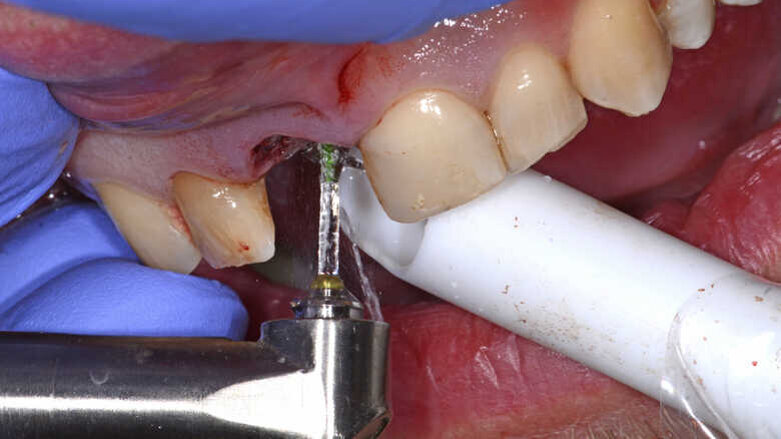

图10. 使用Er:YAG激光治疗仪移除肉芽组织。

前期准备充分后,拔除患牙。患牙骨折吸收区明显可见肉芽组织(图9),使用Er:YAG激光治疗仪将其移除(H14型手持器械,欧洲之星Fotona;图10)。拔牙过程无创伤,创口干洁,可以行种植术(图11)。